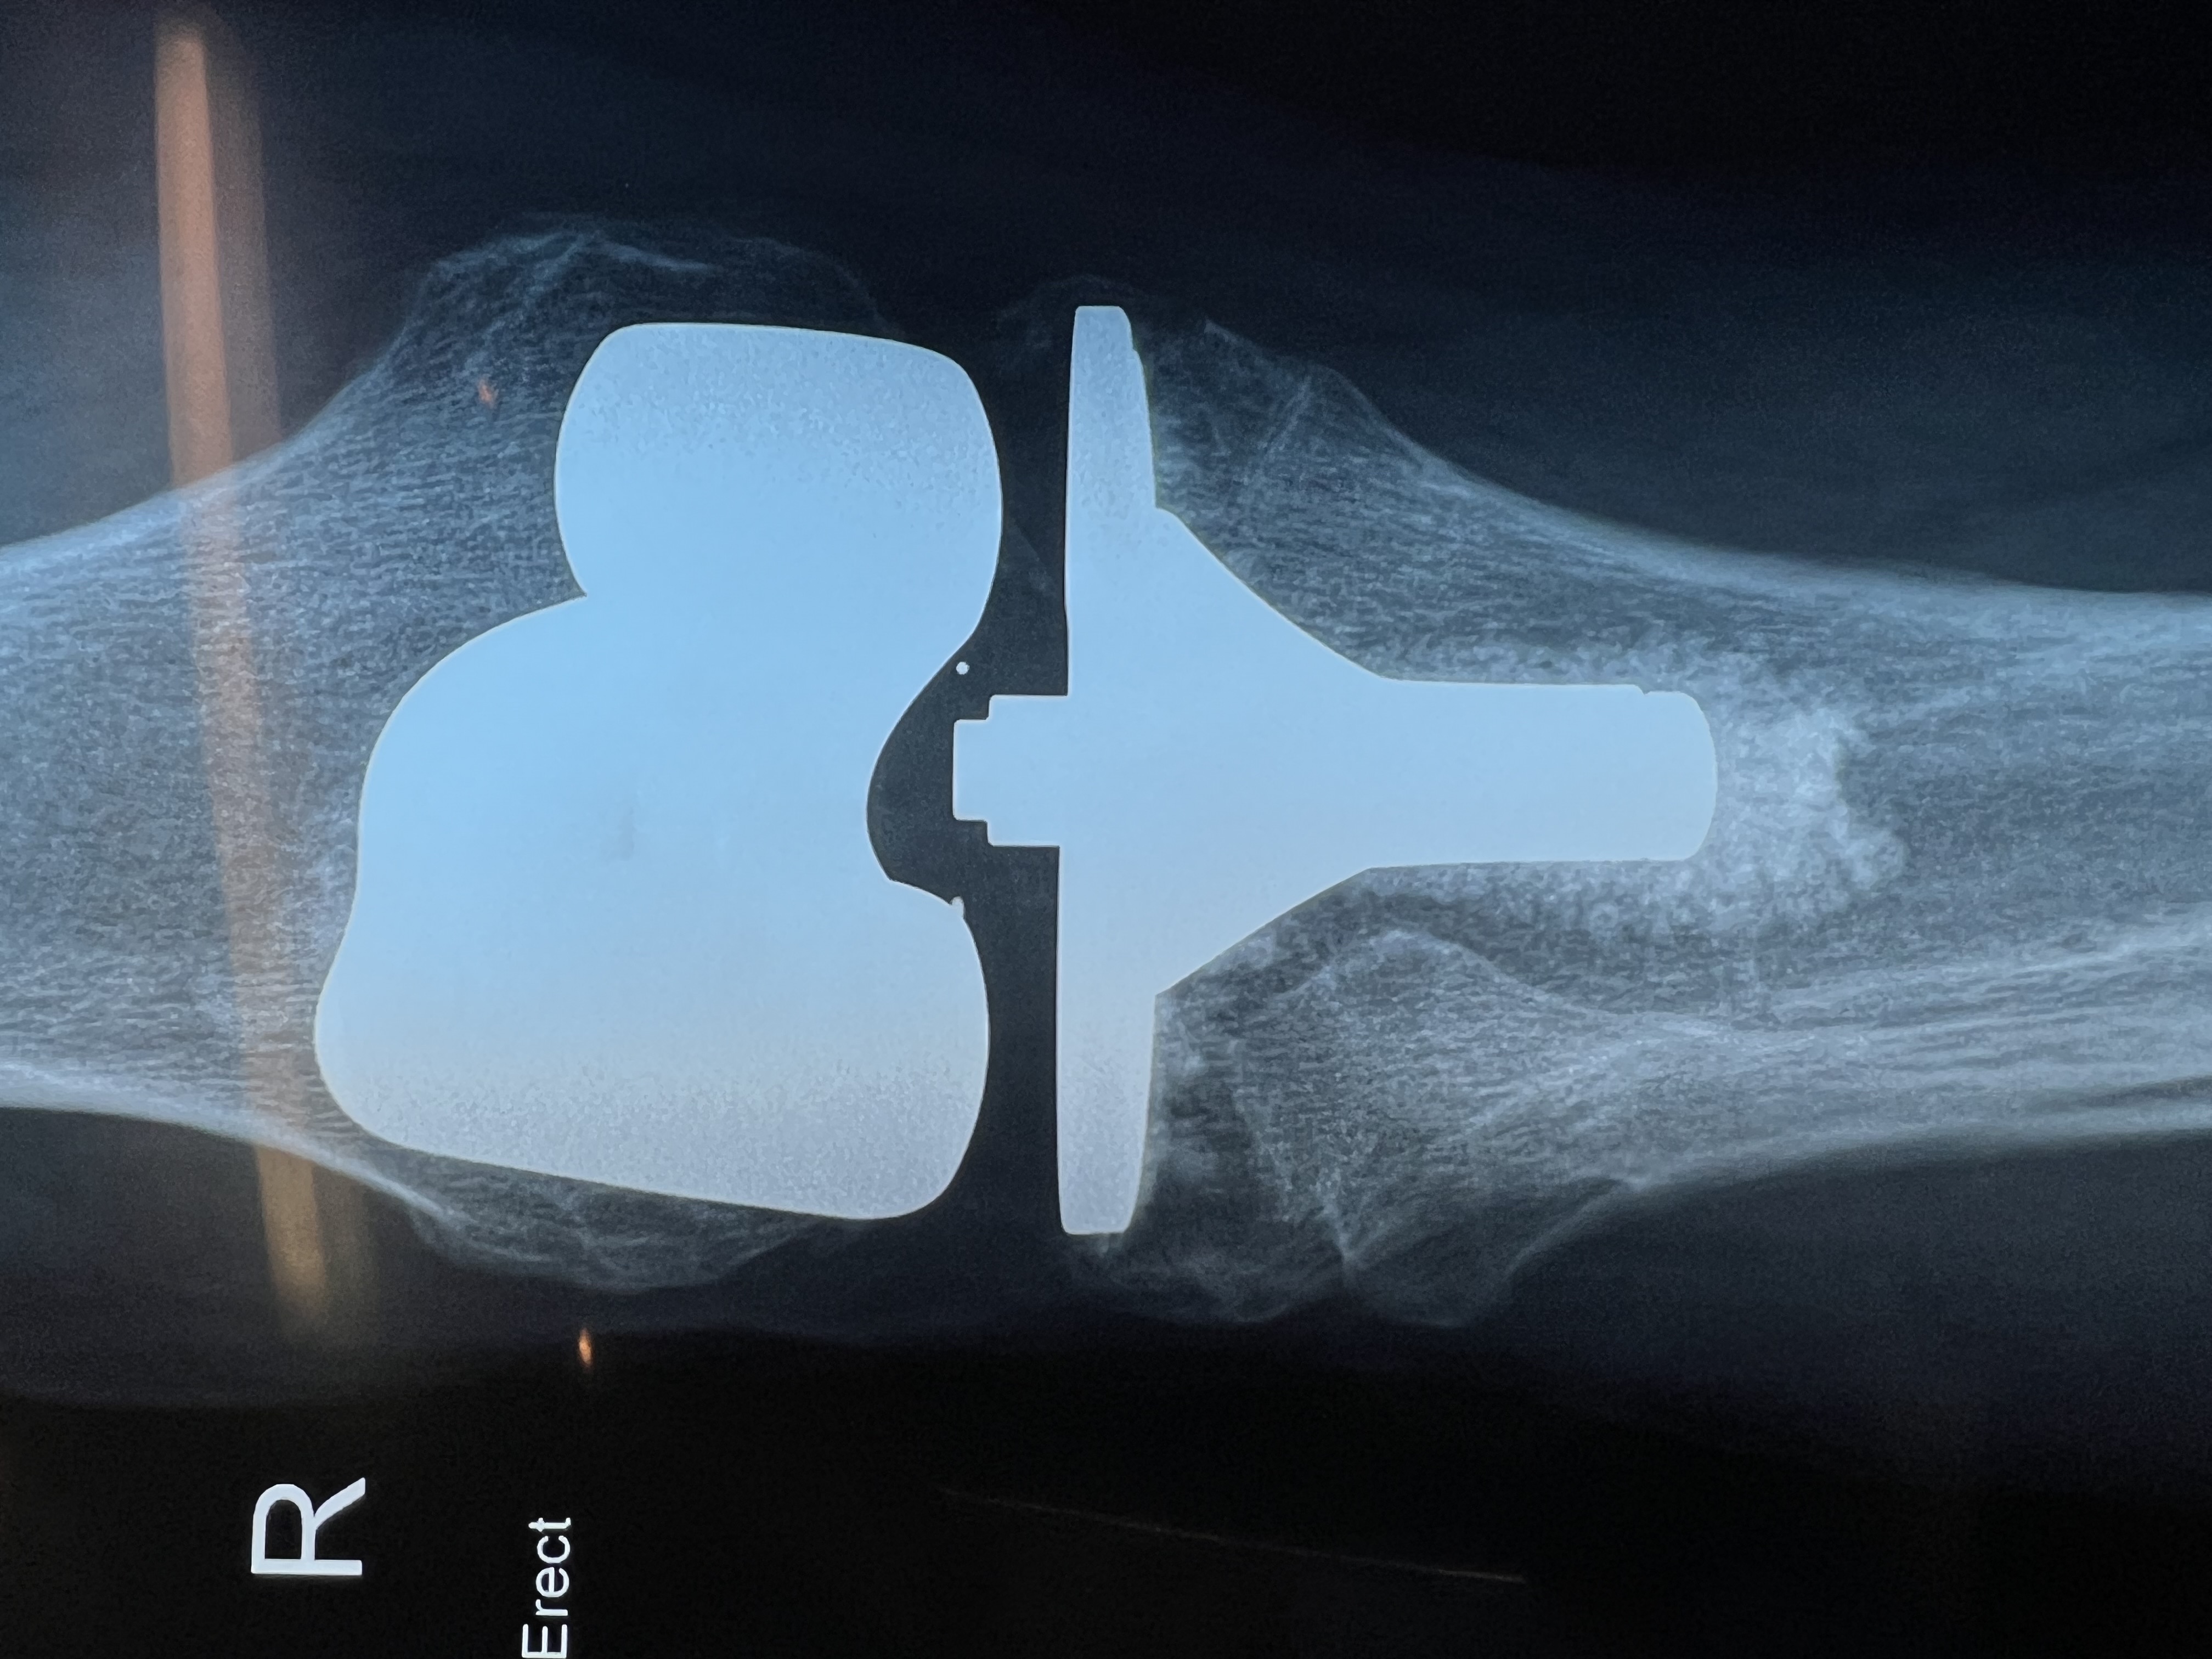

A total knee replacement is a surgery to replace a damaged or worn-out knee joint with an artificial one. It is often done for people with severe arthritis or injuries that cause chronic pain, stiffness, and difficulty walking.

1. Removes the damaged bone and cartilage from the ends of the thigh bone (femur) and shin bone (tibia).

2. Shapes the bones to fit the artificial joint.

3. Attaches the new knee joint, made of metal and plastic, to restore smooth movement.

4. Tests for proper movement and stability before closing the incision.